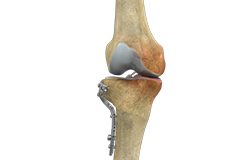

High Tibial Osteotomy

High tibial osteotomy is a surgical procedure performed to relieve pressure on the damaged site of an arthritic knee joint. It is usually performed in arthritic conditions affecting only one side of your knee and the aim is to take pressure off the damaged area and shift it to the other side of your knee with healthy cartilage.